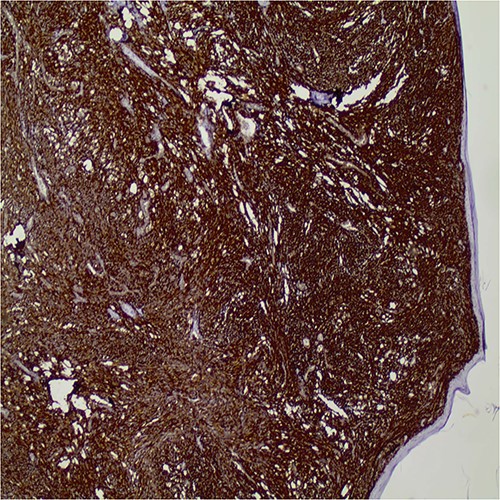

Immunohistochemically, the tumor cells expressed diffuse CD10 positivity (Fig. 3), while they were negative for pancytokeratin, p63, keratin 5/6, MelanA. HMB45 and S-100 were also negative excluding the possibility of sarcomatous carcinoma and melanoma, respectively. The histopathologic and immunohistologic findings were consistent with invasive pleomorphic dermal sarcoma.

Diffuse CD10 expression by the tumor cells (original magnification X40).